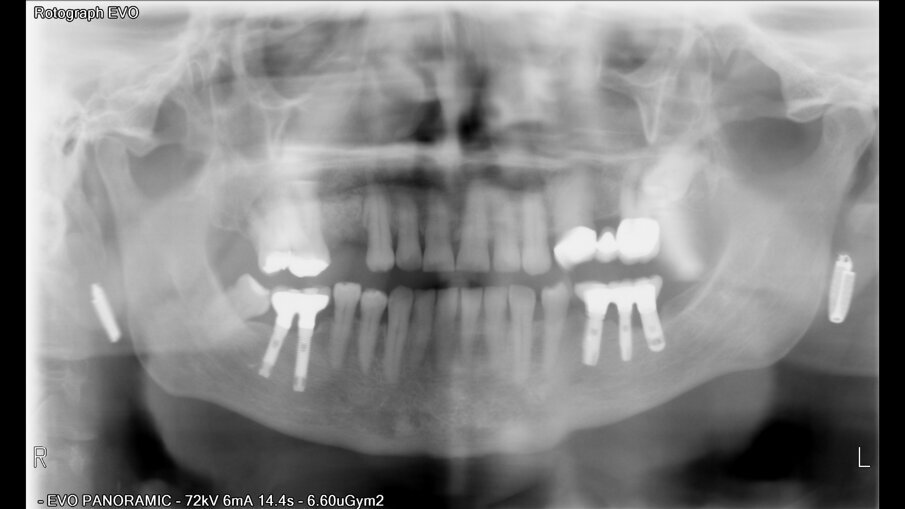

Posuzovali jsme 181 pacientů (97 žen a 121 mužů s průměrným věkem 49,2 let) se 721 implantáty. Z toho bylo zavedeno 384 implantátů na úrovni kosti, 289 zúžených implantátů na úrovni kosti a 48 implantátů na úrovni měkkých tkání (tabulka 2). Implantáty byly klasifikovány podle jejich pozice v horní a dolní čelisti. Pokud jde o anamnézu kouření u pacientů, počet denně vykouřených cigaret se pohyboval mezi 20 a 60 cigaretami.

Po chirurgickém zákroku byly pořízeny periapikální RTG snímky, na nichž byla zkontrolována přesnost zavedení implantátů. Pooperační medikace spočívala v předepsání antibiotik. Digitální RTG snímky byly pořízeny v době chirurgického zákroku, po 24 hodinách a jeden měsíc po zákroku, a to za účelem vyhodnocení úspěšnosti implantologického ošetření. Zánětlivé procesy byly zjištěny u 24,1 % pacientů. V případě potřeby byla provedena augmentace za použití materiálu NanoBone (Artoss), kostní náhražky Geistlich Bio­Oss a membrán Geistlich Bio-Gide (oba produkty Geistlich Biomaterials).

Ze 721 implantátů selhalo celkem 65 implantátů. Míra úspěšnosti tedy ve výsledku byla 90,98 %, tedy nižší než v naší předchozí studii provedené u nekuřáků, u nichž byla míra úspěšnosti 98,70 %.2 U skupiny neúspěšných implantátů selhala většina z nich (74,5 %) dva až čtyři týdny po zavedení v důsledku nedostatečné oseointegrace. Periimplantitida se vyskytovala u 20 % neúspěšných implantátů. To lze přičíst špatné ústní hygieně a tvorbě plaku. U 4,6 % případů se periimplantitida objevila v rozmezí jednoho až tří let po zavedení implantátu v důsledku mechanických problémů po úbytku kosti. Nebyla zjištěna žádná souvislost mezi délkou a průměrem implantátu a mírou selhání, ani mezi počtem vykouřených cigaret a mírou selhání implantátu.